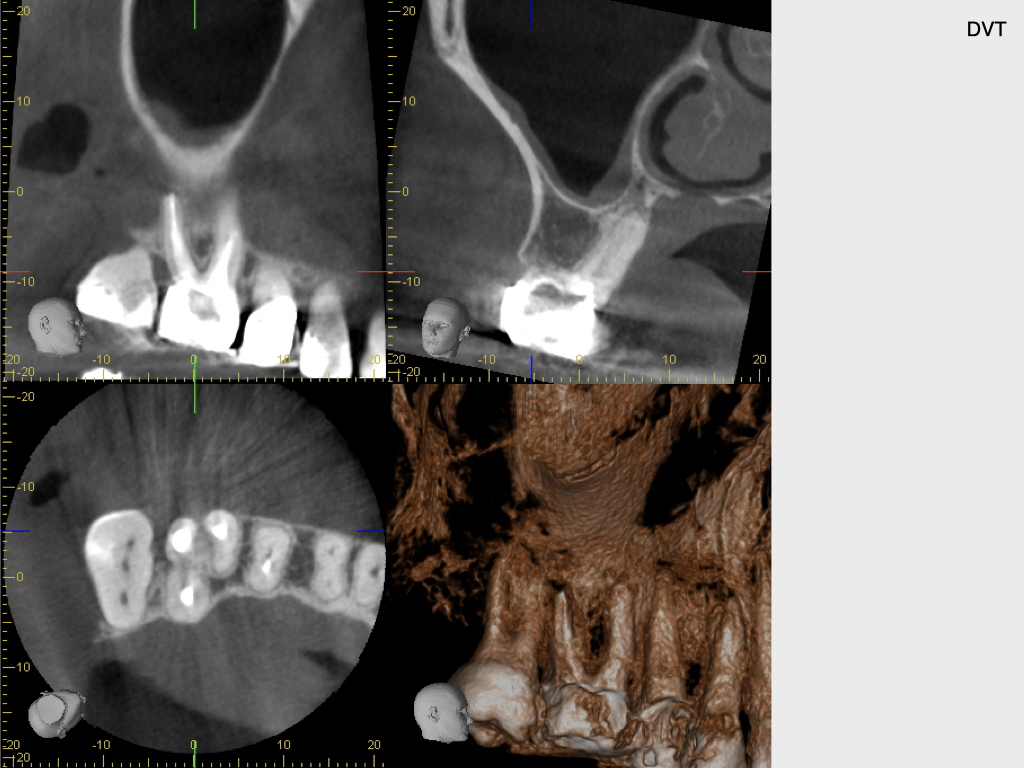

10064.002

1024 × 768

Zahn 16